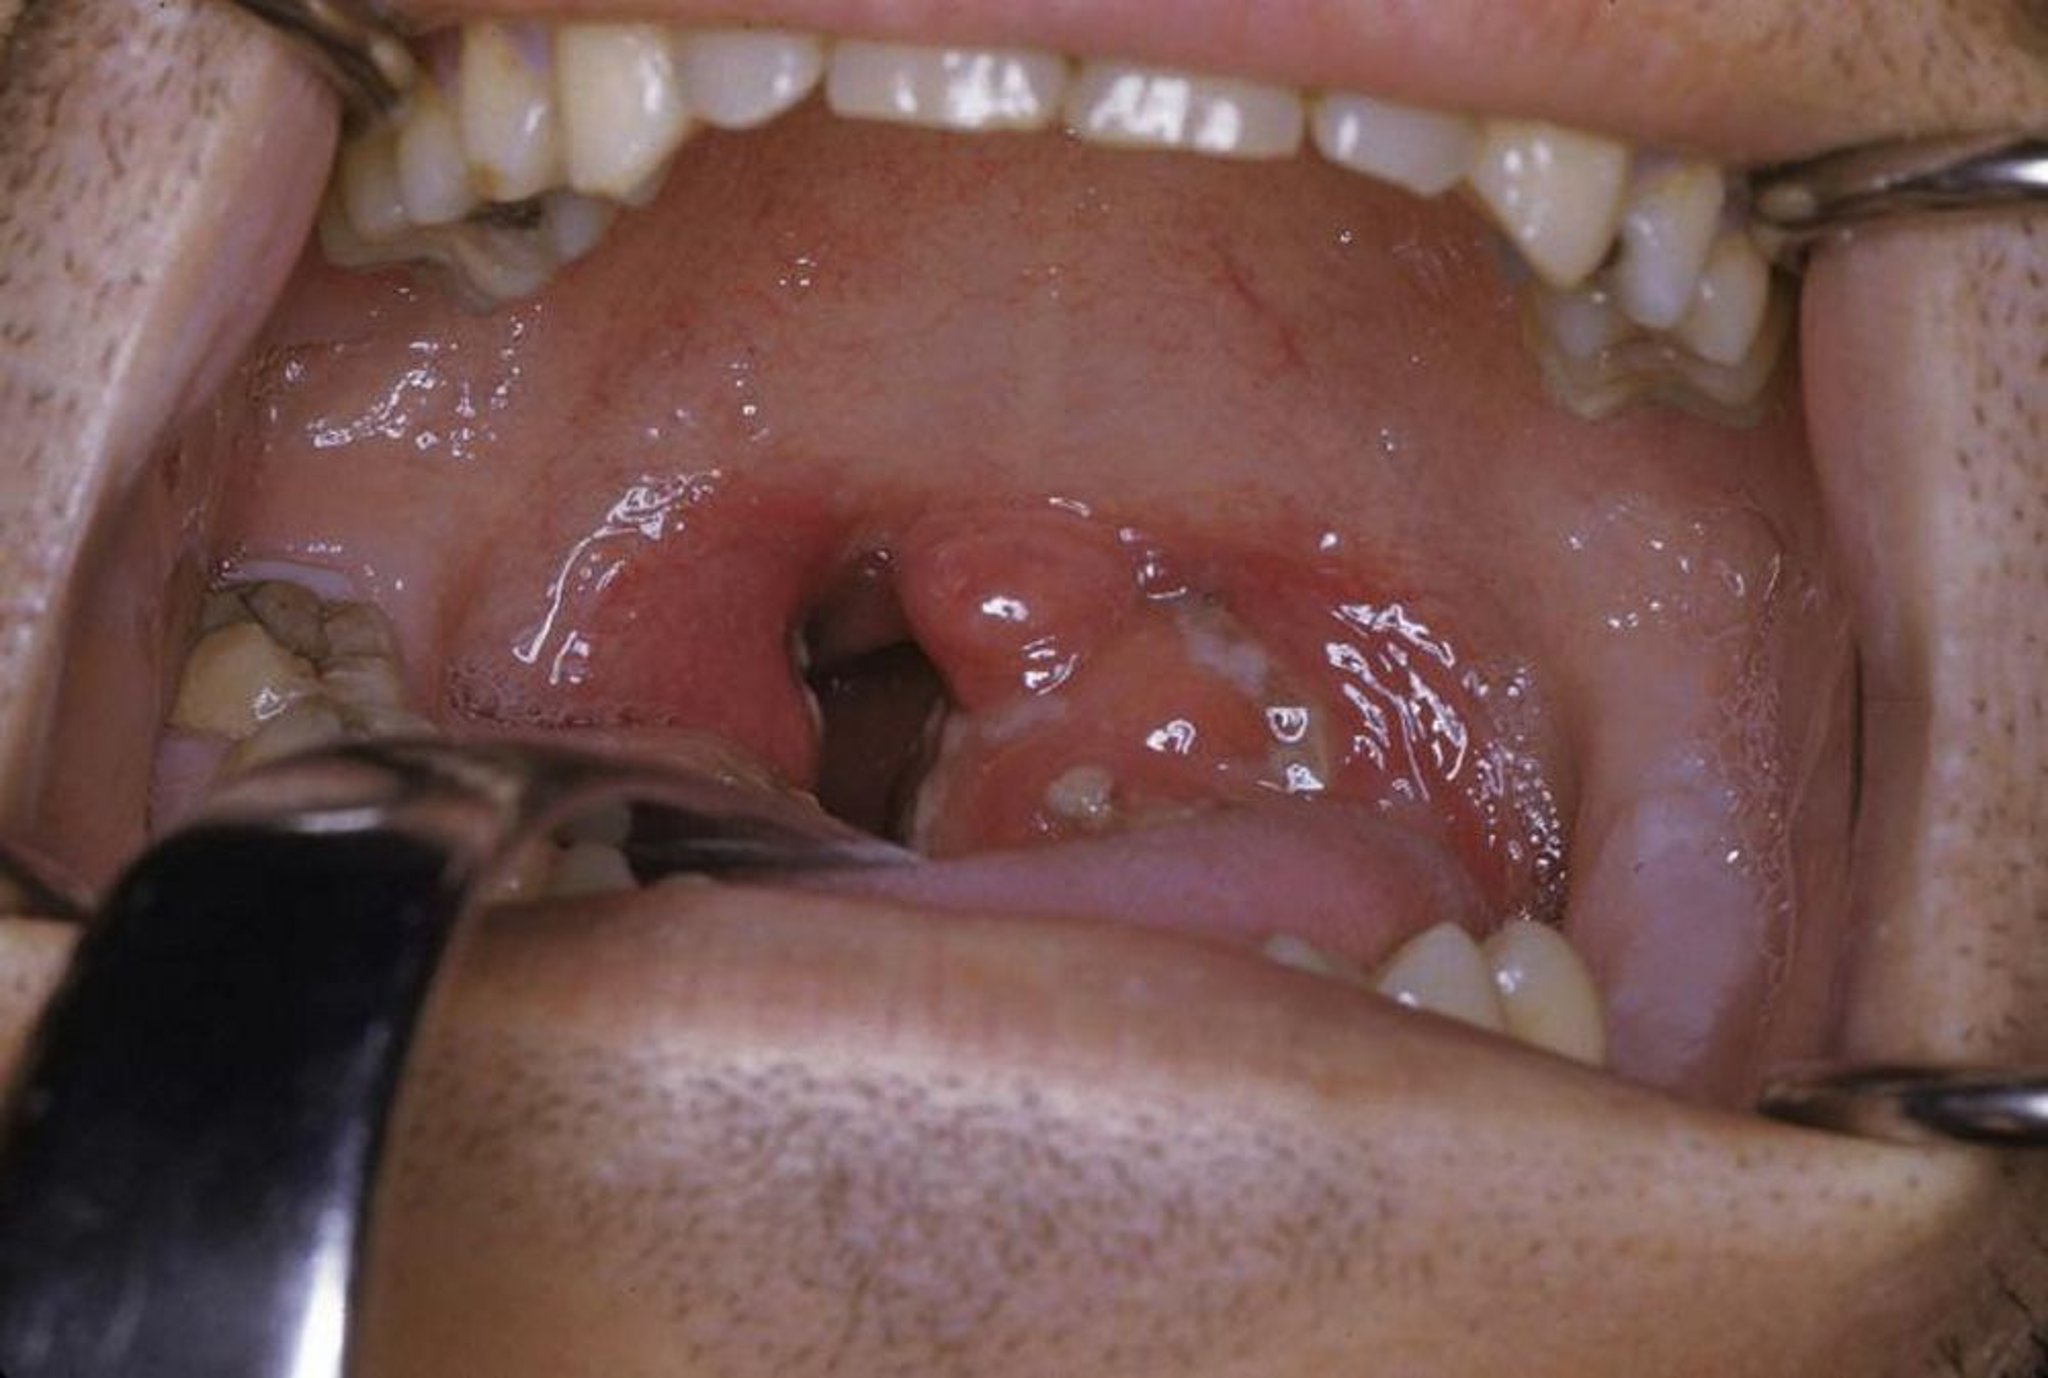

急性扁桃炎

この写真には,滲出液と発赤を伴う急性扁桃炎が写っている。

Photo provided by Clarence T.Sasaki, MD.